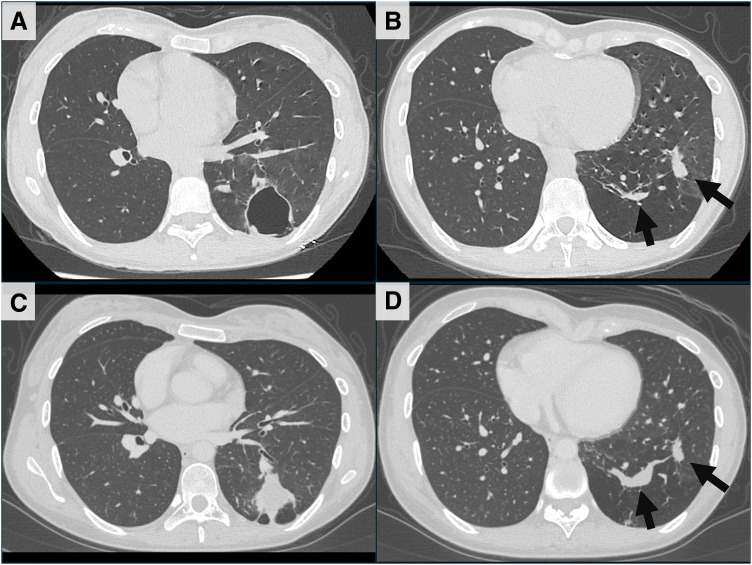

Case presentation: The patient was a 26-year-old woman. A medical checkup chest X-ray showed abnormalities. The patient had no past medical history, including of bleeding tendency or repeated pneumonia, and no familial history of CPAM and PAVM. A chest CT revealed multiple lung cysts (maximum diameter of 40 mm) in the left lower lobe of the lung, and congenital pulmonary cysts were suspected. The chest CT also showed two PAVMs (vessel diameters of 6 mm and 4 mm) in the same left lower lobe. Serum tests were positive for Aspergillus-specific antibodies and β-D-glucan, and pulmonary aspergillosis was diagnosed. An antifungal agent (itraconazole) was administered. However, consolidations had developed 9 months after, and the antifungal agent was changed to voriconazole. Then, the consolidations diminished slightly but nevertheless remained, and one of the PAVMs increased in diameter from 6 mm to 10 mm. A left lower lobectomy under thoracoscopy was performed owing to the uncontrolled infection and the risk of complications with PAVMs. The pathological diagnosis of the pulmonary cysts was CPAM type 1. The patient had no symptoms or complications after the surgery.